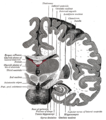

مقطع صورة رنين مغناطيسي لمخ بشري, المهاد مبين فيه. | ||